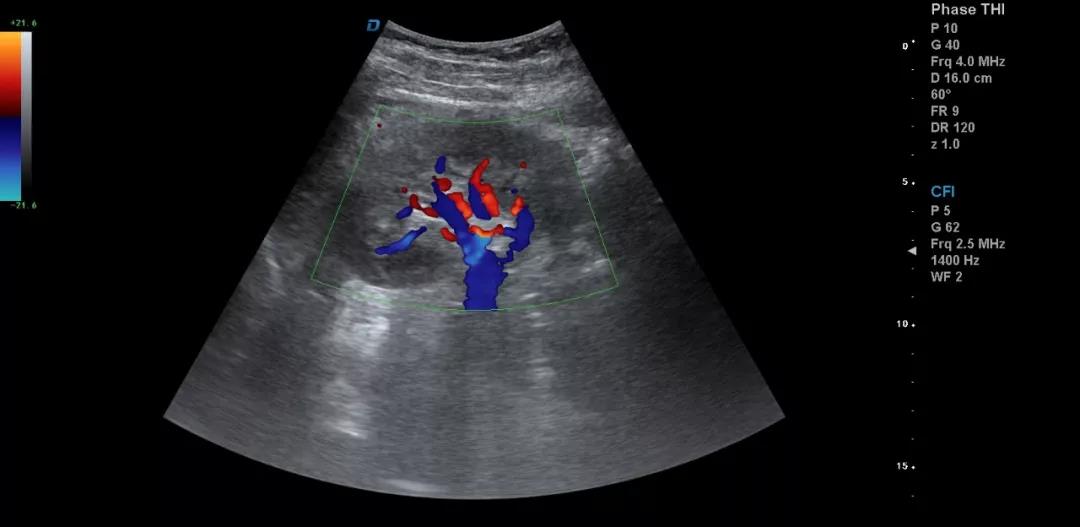

3.注意在工作中積累超聲資料

典型圖片、經典病例圖片、動態影像資料積累的多了分析總結之后就提高了。疑難病例資料積累后,可以隨訪病人,然后總結得到的臨床資料和病理結果。